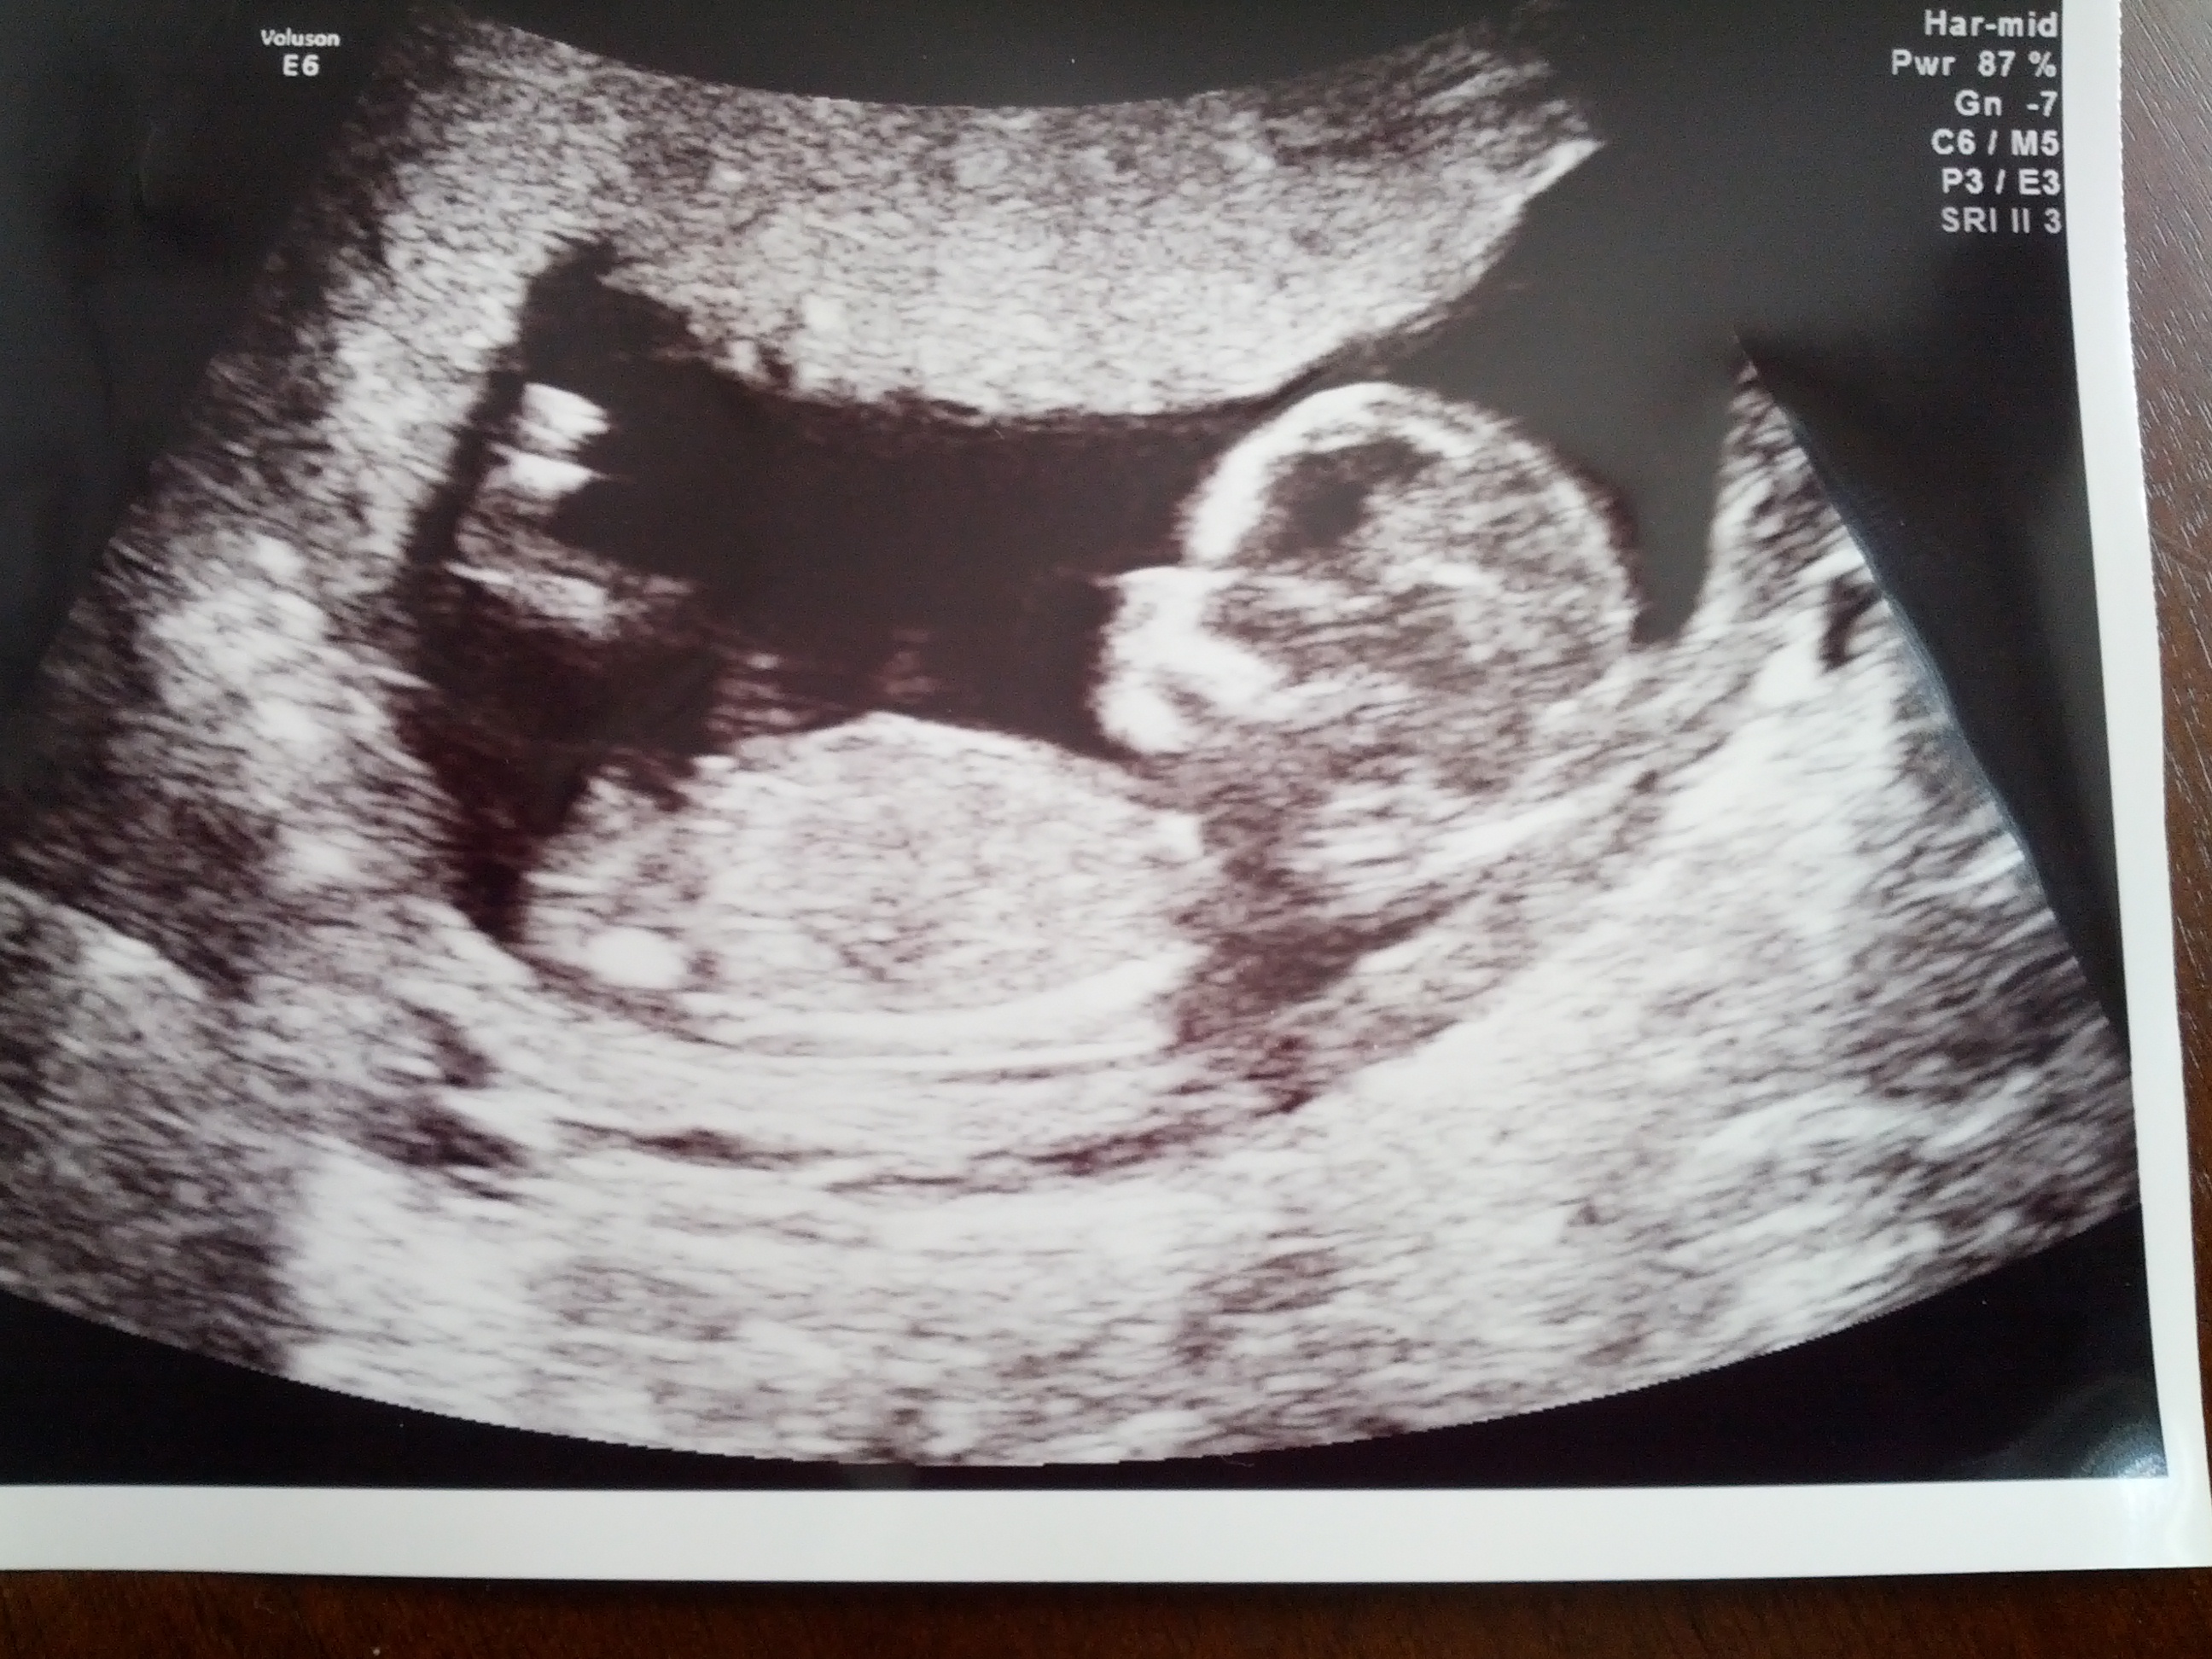

Here they are....very obvious to me and the tech. She did a potty shot and there was something between the legs that she was 50/50 on and that it wasn't as prominent as most boys she sees. Then, the nub said it all.

Attachment 5295